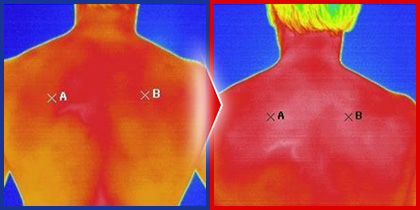

約5分の施術で身体の表面温度が劇的に上昇。

この方は施術後、今までできなかった正座もできるように。

医学博士の研究所や医科歯科大学にある臨床試験会社を使い、施術前後での[血流の変化][末梢血管の本数の変化]など、あらゆる客観的な指標を確認。それに伴う[体温の変化]なども別途臨床試験で客観的に証明されています。

手のひらでは平均29.8度→31.5度まで上昇

体温が上昇するのは、自律神経が整った証拠。自律神経が整えば、精神疾患から内臓機能の低下まであらゆる症状を根本から改善できる。逆にどんなに体を調整しても、自律神経が乱れていると症状は良くならない。1度の施術で体温を確実に上昇できると、治療のレベルは格段にアップします。

※上記資料は2013年に行われた「篠崎式施術による血流・身体バランス改善効果検証試験」から抜粋したものです。今回は、当時よりさらに改良された手技の発表になります。